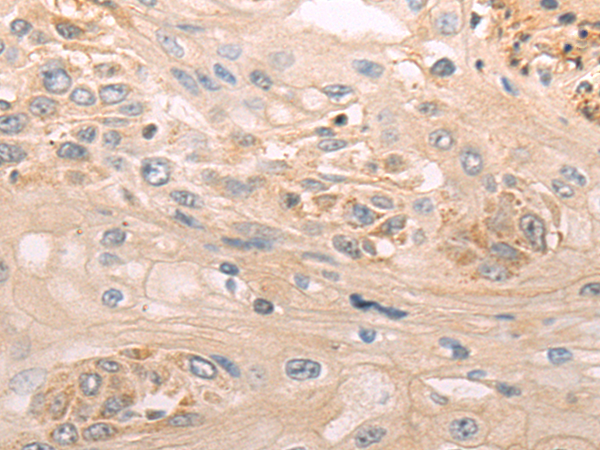

分类: 科研抗体货号: P05034别名: CT7; CT7.1应用: IHC反应种属: Human